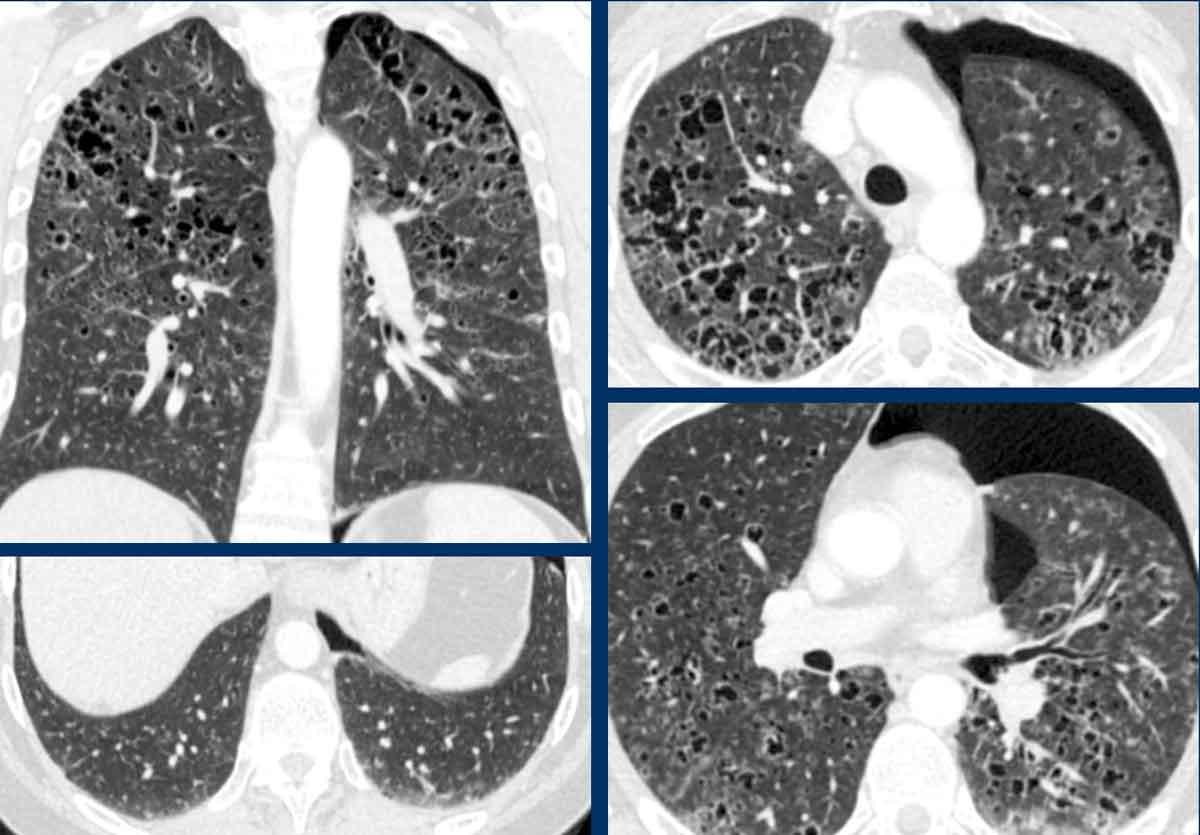

LIP – Viêm Phổi Kẽ Dạng Lympho (Lymphoid Interstitial Pneumonia)

Viêm phổi kẽ dạng lympho (LIP) là một bệnh phổi kẽ chưa rõ căn nguyên, đặc trưng bởi sự thâm nhiễm của các tế bào lympho.

Bệnh có liên quan đến các bệnh lý hệ thống (đặc biệt là hội chứng Sjögren).

Biểu hiện có thể chỉ là các nang đơn thuần, nhưng thường gặp hơn là sự kết hợp với kính mờ, lưới hóa và/hoặc các nốt. Một số nang có thể có vách ngăn mờ nhạt, có thể bắt chước hình ảnh chấm trung tâm như thấy trong khí phế thũng (Hình 1 và 4).

Hình ảnh

- Các nang đơn thuần trong nền kính mờ lan tỏa.

- Các nang đơn thuần trong LIP. Đôi khi có thể thấy các lõm mạch máu hoặc vách ngăn. Các vách ngăn này có thể bắt chước hình ảnh chấm trung tâm như trong khí phế thũng trung tiểu thùy.

- Các nang đơn thuần trong vùng kính mờ.

- Các nang đơn thuần kèm lưới hóa mờ nhạt và kính mờ.

Các hình ảnh này của một nam bệnh nhân 55 tuổi có triệu chứng khó thở.

Bệnh nhân có tiền sử bệnh mô liên kết hỗn hợp (MCTD) và không hút thuốc lá.

Nhận xét

Dấu hiệu đặc trưng nhất là sự kết hợp giữa các nang và kính mờ.

Bàn luận

Chẩn đoán có khả năng nhất dựa trên các dấu hiệu hình ảnh là LIP.

Tiền sử bệnh mô liên kết hỗn hợp cũng là yếu tố gợi ý quan trọng.

Chẩn đoán viêm phổi kẽ bong vảy (DIP) ít có khả năng, do bệnh nhân không hút thuốc lá và trong DIP tất cả các nang phải nằm trong vùng kính mờ. Trong trường hợp này, một trong các nang rõ ràng nằm trong vùng nhu mô phổi bình thường (mũi tên).

Các hình ảnh này của một nữ bệnh nhân 60 tuổi mắc bệnh Sjögren, được chỉ định chụp HRCT để tầm soát bệnh phổi kẽ.

Có một vài nang (nhiều hơn bốn nang, không hiển thị hết), do đó nhiều khả năng đây là bệnh phổi dạng nang. Có một vùng kính mờ ở các trường phổi dưới và một số vách gian tiểu thùy dày.

Sự kết hợp giữa các nang và kính mờ giúp thu hẹp chẩn đoán phân biệt còn LIP và DIP.

Ở bệnh nhân mắc bệnh Sjögren, chẩn đoán là LIP.